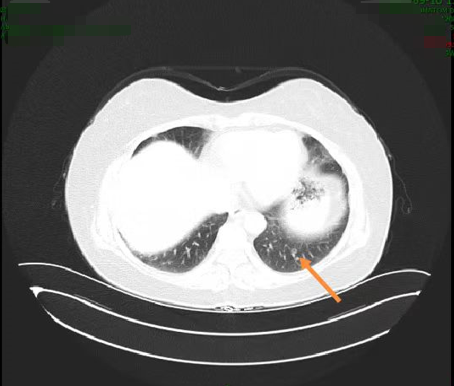

患者于2020年9月17日复查胸腹部CT示双肺可见多发小结节及空洞,部分病灶较前(2020年4月2日)增大,转移不除外(图2);双肺少许炎症;肝内小囊肿可能;左侧肾上腺增粗;直肠术后所见。